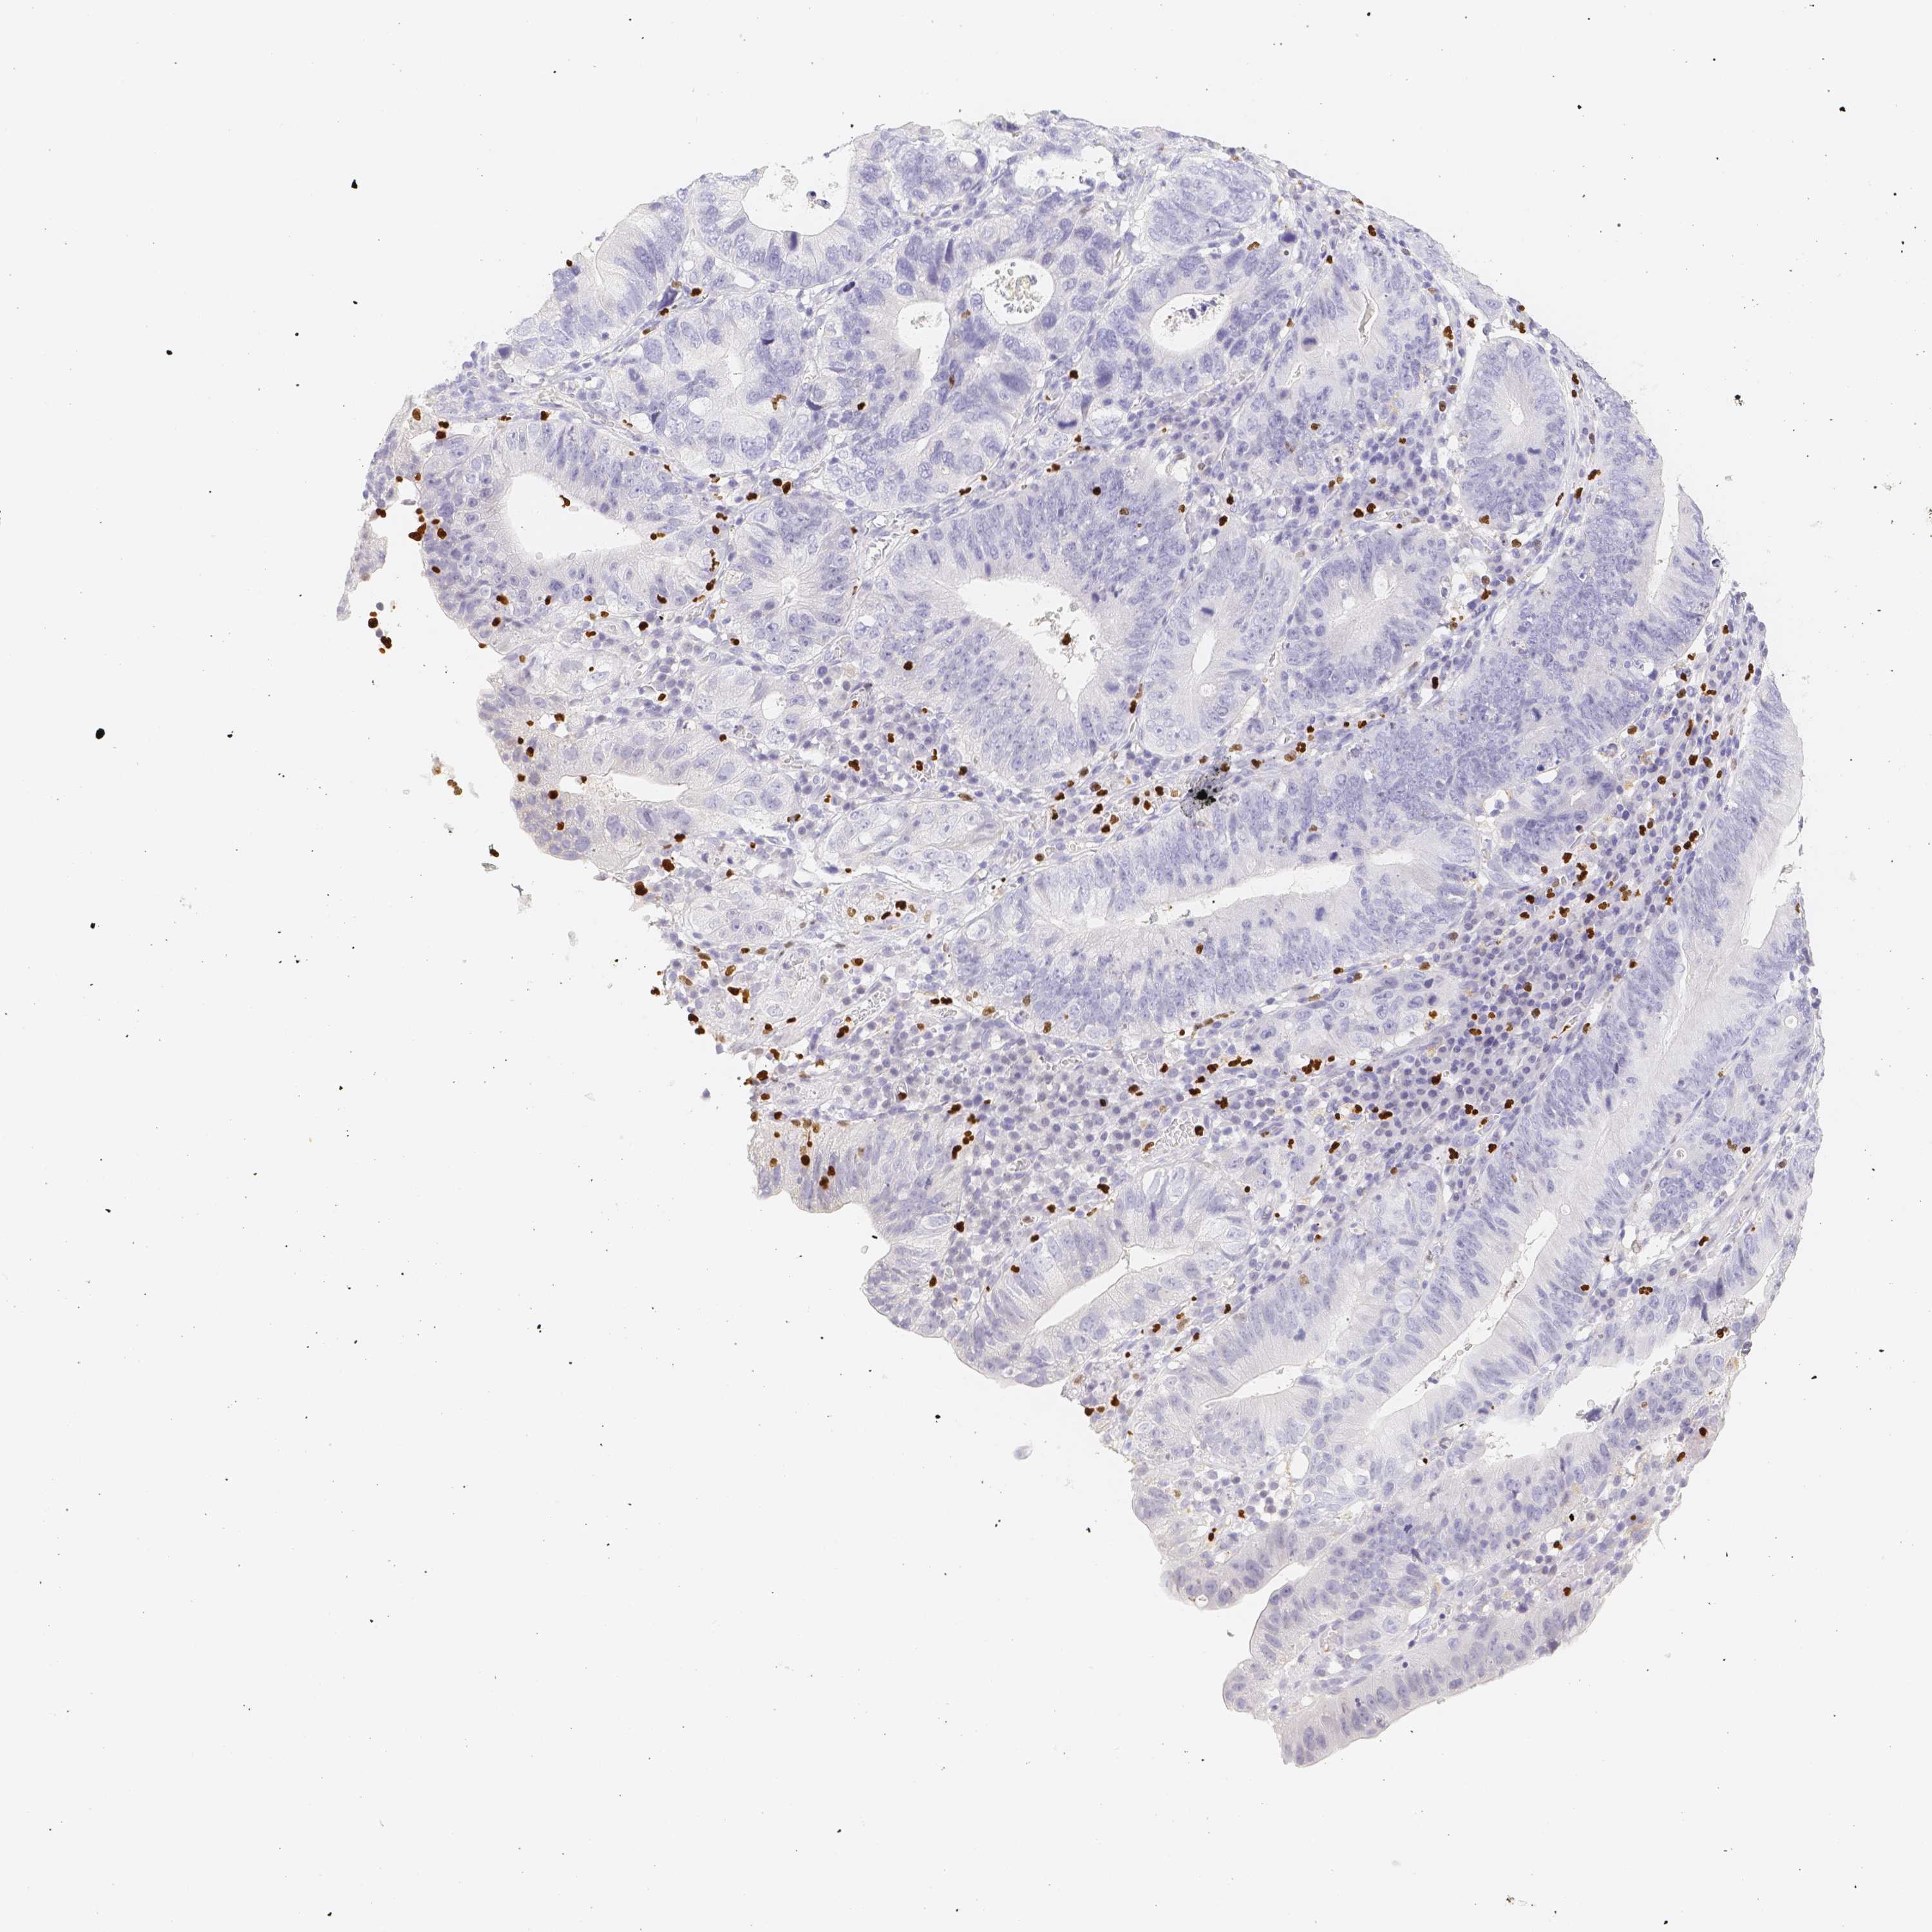

STOMACH CANCER - Protein expressioni

A mouse-over function shows sample information and annotation data. Click on an image to view it in a full screen mode. Samples can be filtered based on level of antibody staining by selecting one or several of the following categories: high, medium, low and not detected. The assay and annotation is described here.

Antibody stainingi

Antibody staining in the annotated cell types in the current human tissue is reported as not detected, low, medium, or high, based on conventional immunohistochemistry profiling in selected tissues. This score is based on the combination of the staining intensity and fraction of stained cells.

Each image is clickable and will lead to virtual microscopy that enables deeper exploration of all samples and also displays staining intensity scores, fraction scores and subcellular localization as well as patient and tissue information for each sample.

Antibody HPA017007

Antibody HPA042825

Staining

High

Medium

Low

Not detected

Intensity

Strong

Moderate

Weak

Negative

Quantity

>75%

75%-25%

<25%

None

Location

Nuclear

Cytoplasmic/membranous

Cytoplasmic/membranous,nuclear

Adenocarcinoma, NOS